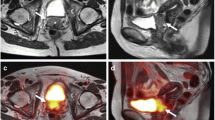

For the two patients with rectal staging, both imaging modalities showed no evidence of loco-regional lymph node metastasis or distant metastasis. Unlike PET/CT, however, PET/MRI provided detailed T staging showing a T3 rectal lesion in both patients as well as mesorectal fascia involvement in one patient (Fig. 1), which was supported by histopathology and endoscopic ultrasound. These patients underwent neoadjuvant chemoradiation followed by surgical resection. With staging and restaging patients combined, PET/MRI shows at least comparable accuracy in N and M staging/restaging to PET/CT. On a per-patient basis, the true positive rate was 5/7 (71%) for PET/CT and 6/7 (86%) for PET/MRI, and true negative rate was 5/5 (100%) for both modalities. The false negative rate of 14% (one of seven patients) for PET/MRI was attributed to the fact that it missed to diagnose liver metastases in one patient. The false negative rate of 29% (two of seven patients) was higher for PET/CT because it failed to diagnosis rectal and perirectal metastatic implants in one additional patient, which was correctly identified by PET/MRI, Fig. 2. Both PET/CT and PET/MRI failed to identify early signs of liver metastases in one patient, in which the MR examination of the abdomen 3 months later showed several new contrast-enhanced liver lesions; subsequent core biopsy confirmed metastatic liver disease. In retrospect, there was one subcapsular 6 mm contrast-enhancing lesion in the right liver lobe on mDIXON images that did not show FDG avidity. The MRI protocol was however not optimized for liver imaging in this patient, lacking the high-resolution MR images.

72-year-old man with a history of pT3N0M0 rectosigmoid colon carcinoma and rising CEA levels was referred for restaging with PET/CT 22 months after initial diagnosis. PET/CT images—axial PET (A), CT (B), fused PET/CT (C)—show a 1.3 × 1.0 cm2, intensely FDG avid presacral lymph node (arrowhead, SUVmax 14.1) with evidence of erosion of S1 (arrow). PET/MR images—axial PET (D), T2W TSE (E), fused PET/T2W TSE (F), and DWI (G)—demonstrate the FDG avid lesion (SUVmax 13.6) in the same region (arrowhead) but there is no visible erosion of S1. There are several larger FDG avid mesenteric lymph nodes in this region at both modalities, not shown. PET/CT was acquired before PET/MR with a delay of 64 min.